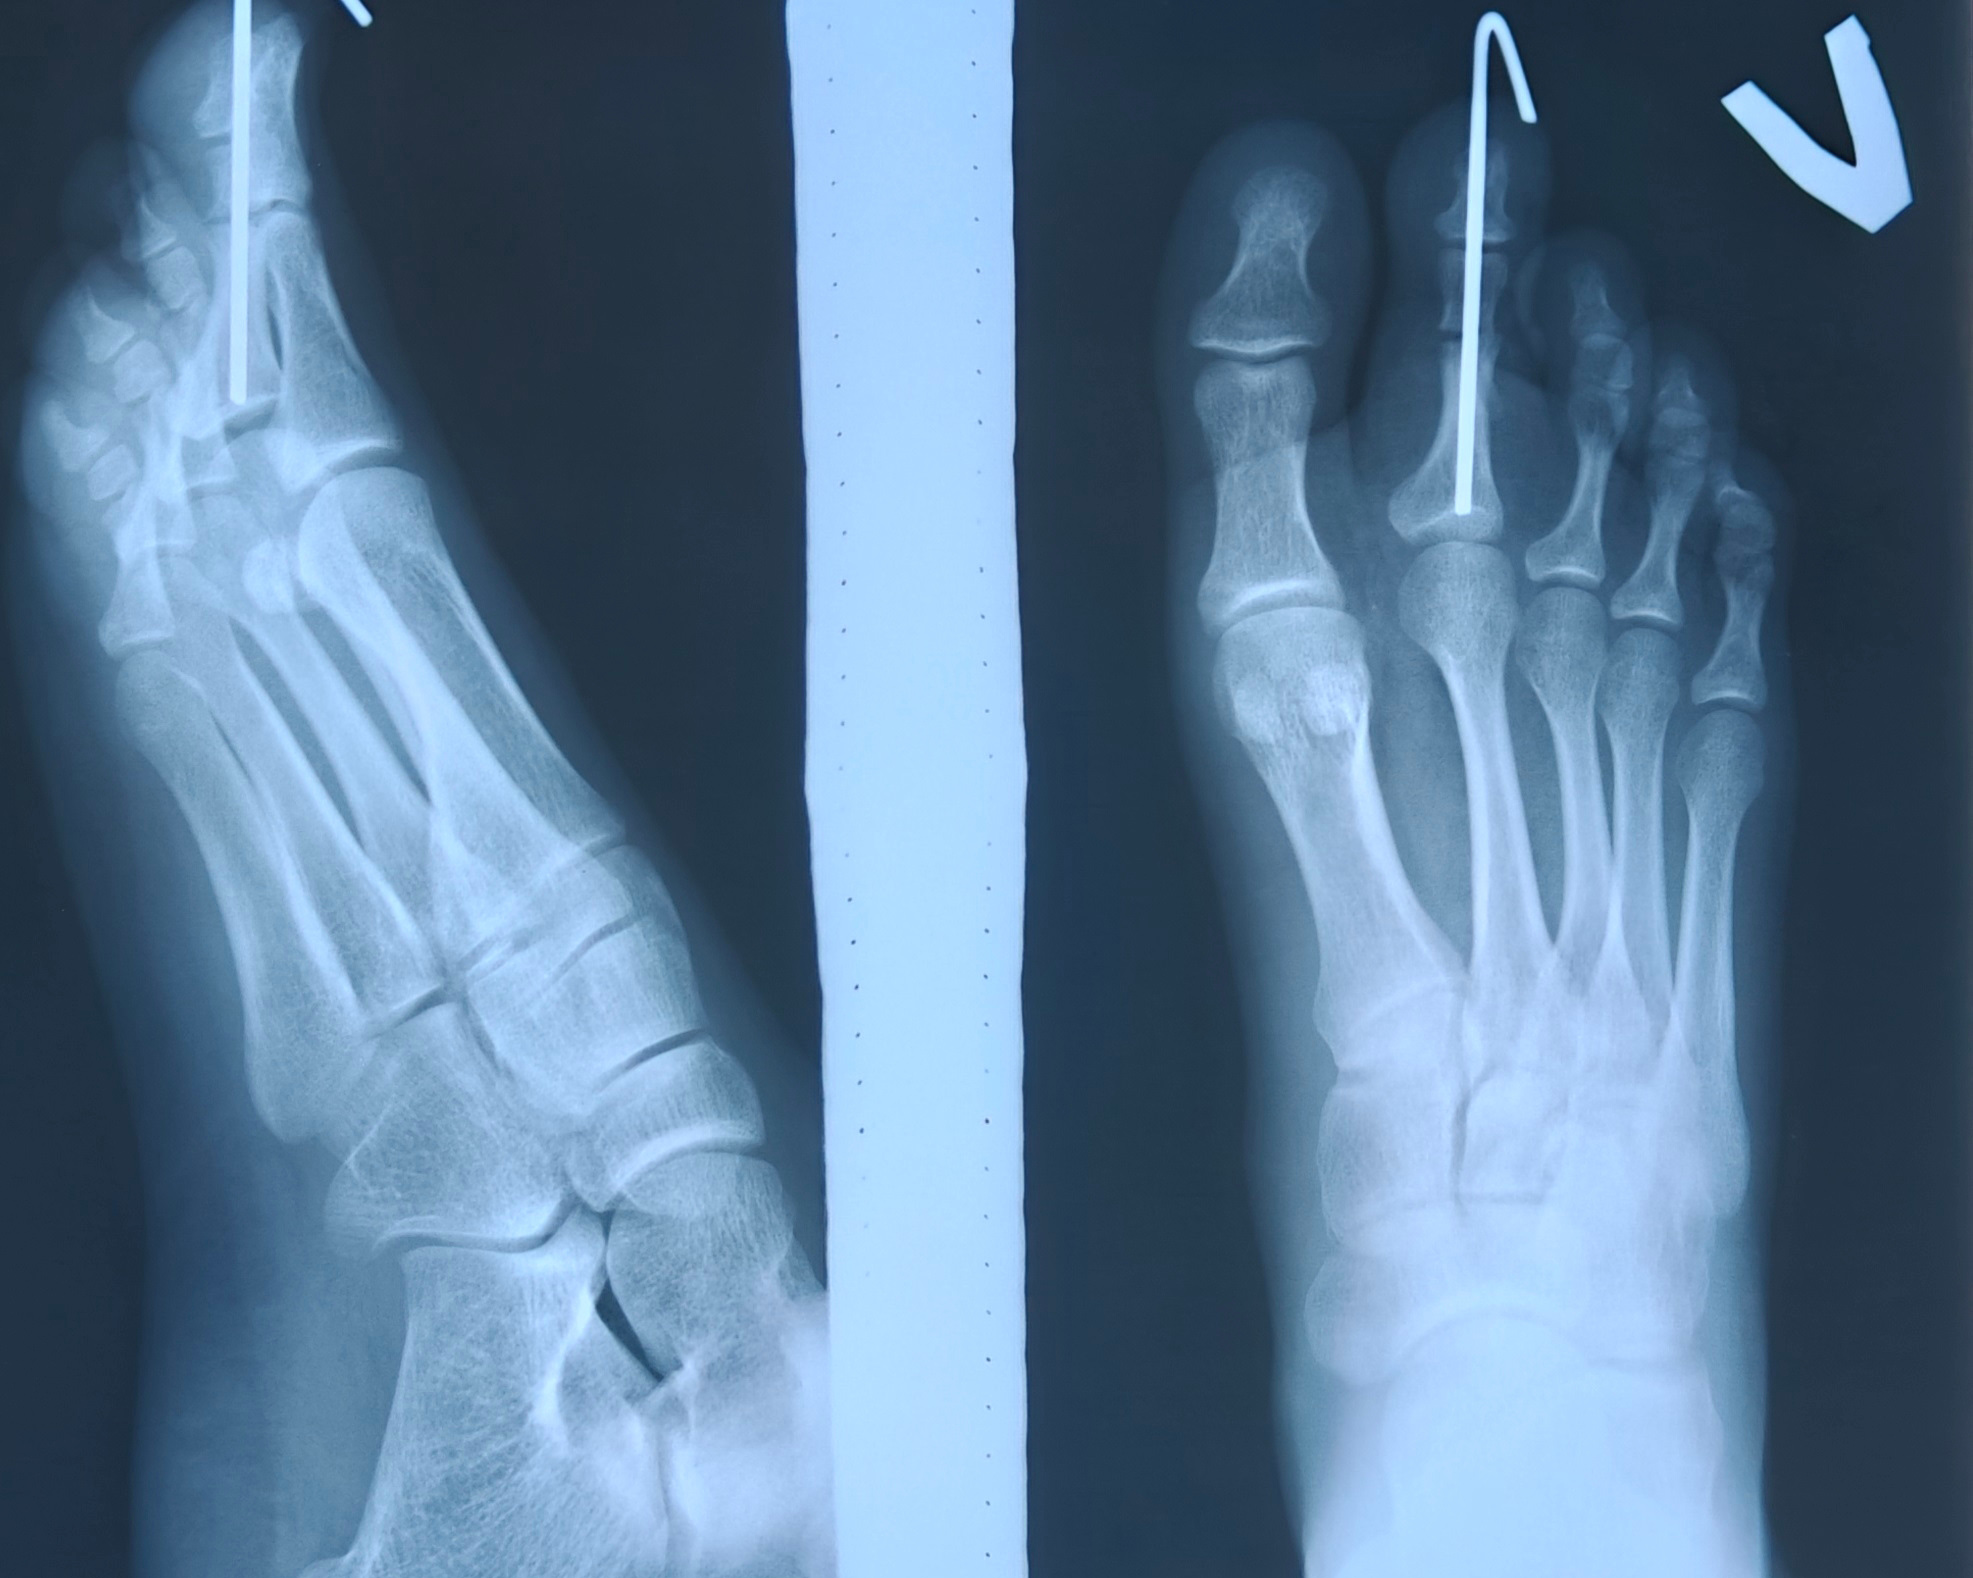

В ходе операции пациентке была выполнена реконструкция II пальца стопы - укорачивающая остеотомия с фиксаций костных фрагментов спицей и удаление избыточных мягких тканей.

«В результате оперативного вмешательства был сформирован косметически и функционально полноценный палец, к невероятному восторгу и огромной благодарности пациентки врачам отделения и всей операционной бригаде», - рассказывают в Пигановском центре спецмедпомощи.